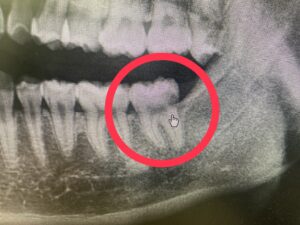

横向き親知らずとは?

親知らずが横に倒れて生え、手前の歯(7番目の歯)にぶつかっている状態です。

多くの場合、歯ぐきや骨の中に一部埋まっています。

① 手前の歯が虫歯になる

親知らずとの間に汚れが溜まりやすく、

気づいたときには大きな虫歯になっていることがあります。

手前の歯の神経治療が必要になることも。。。